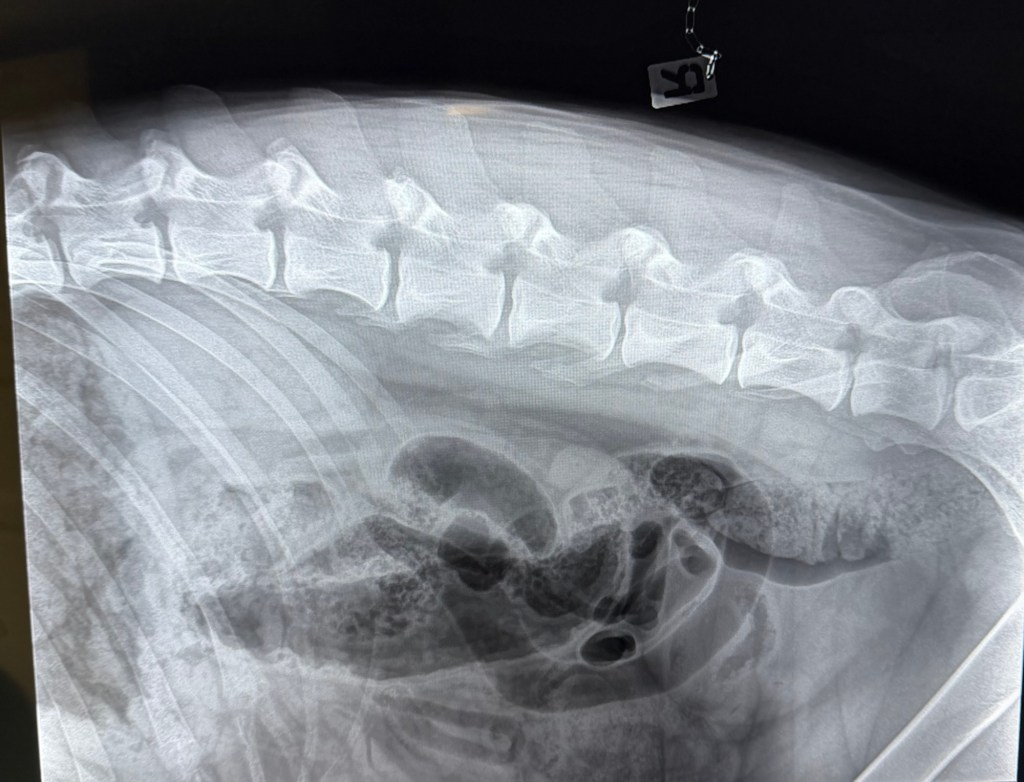

Freki har også vært på røntgen nå i november 2025, i en alder av 3år og 8måneder. Dette grunnet et ønske om å avdekke eventuelle svakheter eller forandringer i skjelett. Freki er en kraftig og stor hund med mye muskler og kraft, så her er det store påkjenninger. Rygg og albuer ble sjekket og resultatene var fantastiske og meget bra! Han har mikroskopiske forandringer i rygg og en flott bakpart med robust lende-rygg. Albuene er som tidligere, uten stor signifikant forandring. En frisk og sunn 4 åring! Freki har et utrolig flott vesen og er en ordentlig glad Bamse-gutt med masse kjærlighet til alle.